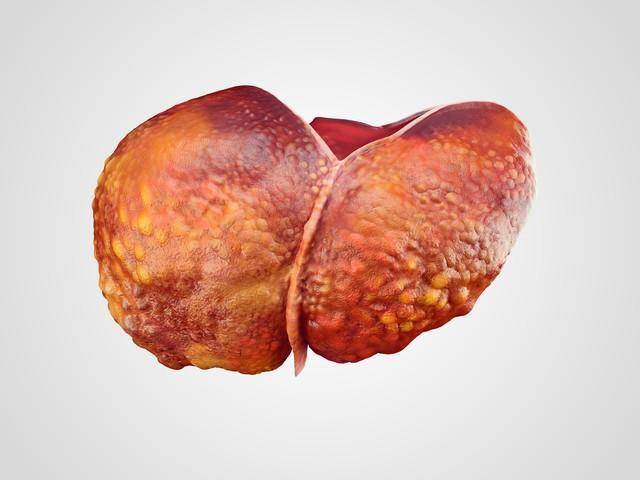

作为一名从医多年的医生,我在临床实践中遇到了许多因不良饮食习惯而导致的肝脏问题病例。肝脏是我们身体中的“化学工厂”,负责代谢和解毒。

然而,一些日常食物对肝脏有着潜在的危害,长期食用可能会导致严重的肝脏疾病。以下是我总结的“毁肝王”食物清单,以及一些真实病例,希望能引起大家的重视。

在我的临床实践中,我曾遇到一个病例,患者是一位中年男士,长期食用高脂肪食品,如油炸食物和含有大量动物脂肪的食品。

他因为肝脏功能异常而来求诊断,检查发现其患有非酒精性脂肪肝病。这种病症主要是由于过多的脂肪积累在肝脏中造成的,长期下去可能会导致肝硬化甚至肝癌。